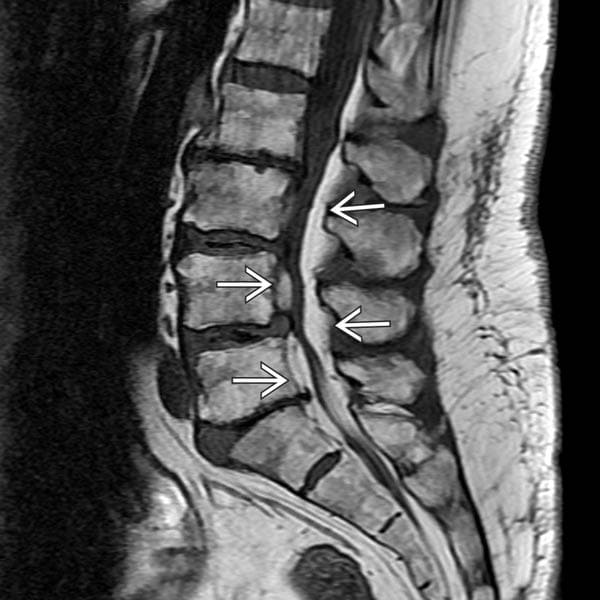

La resonancia magnética es la prueba que mejor nos permite visualizar la grasa epidural. Habitualmente la grasa epidural ocupa un 27% del diámetro del canal, sin embargo en los casos de lipomatosis epidural puede llegar a un porcentaje del 70%.

La compresión producida por la grasa provoca que la médula adopte una forma de Y.